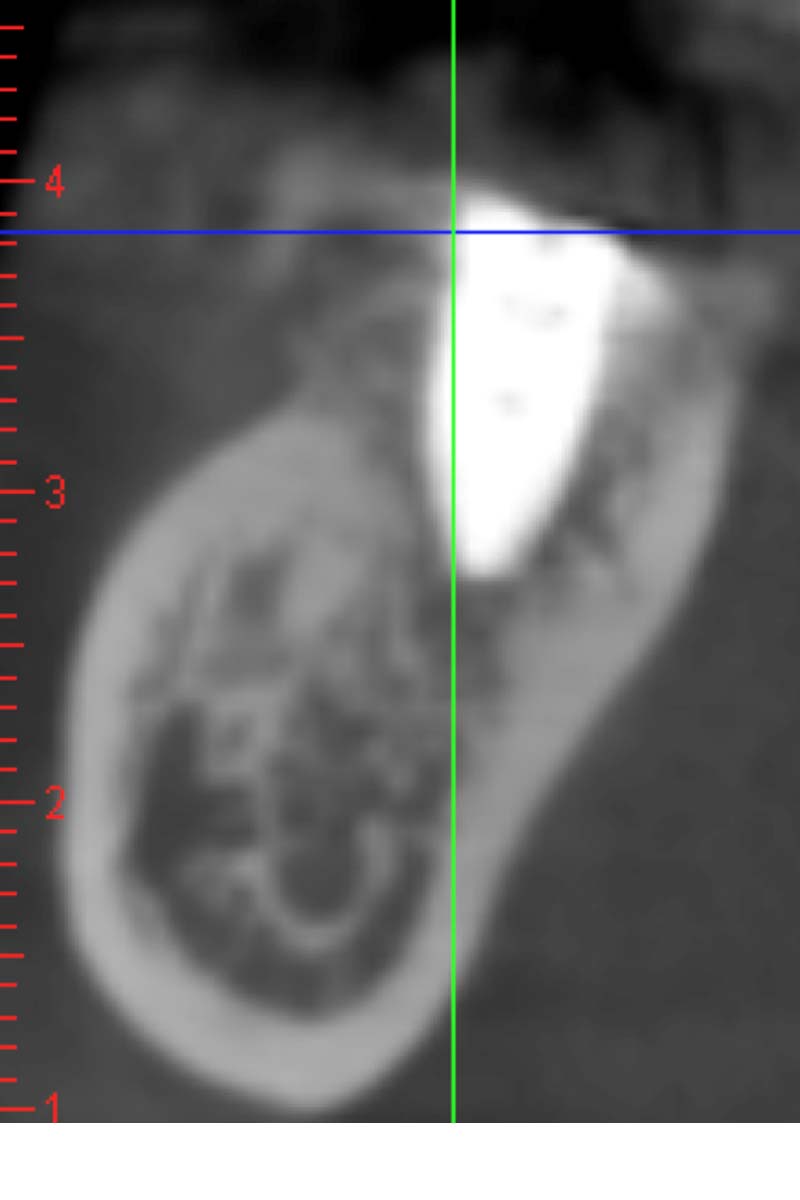

圖例為案例分享:

術前

帳棚釘+骨粉+再生膜術後7個月